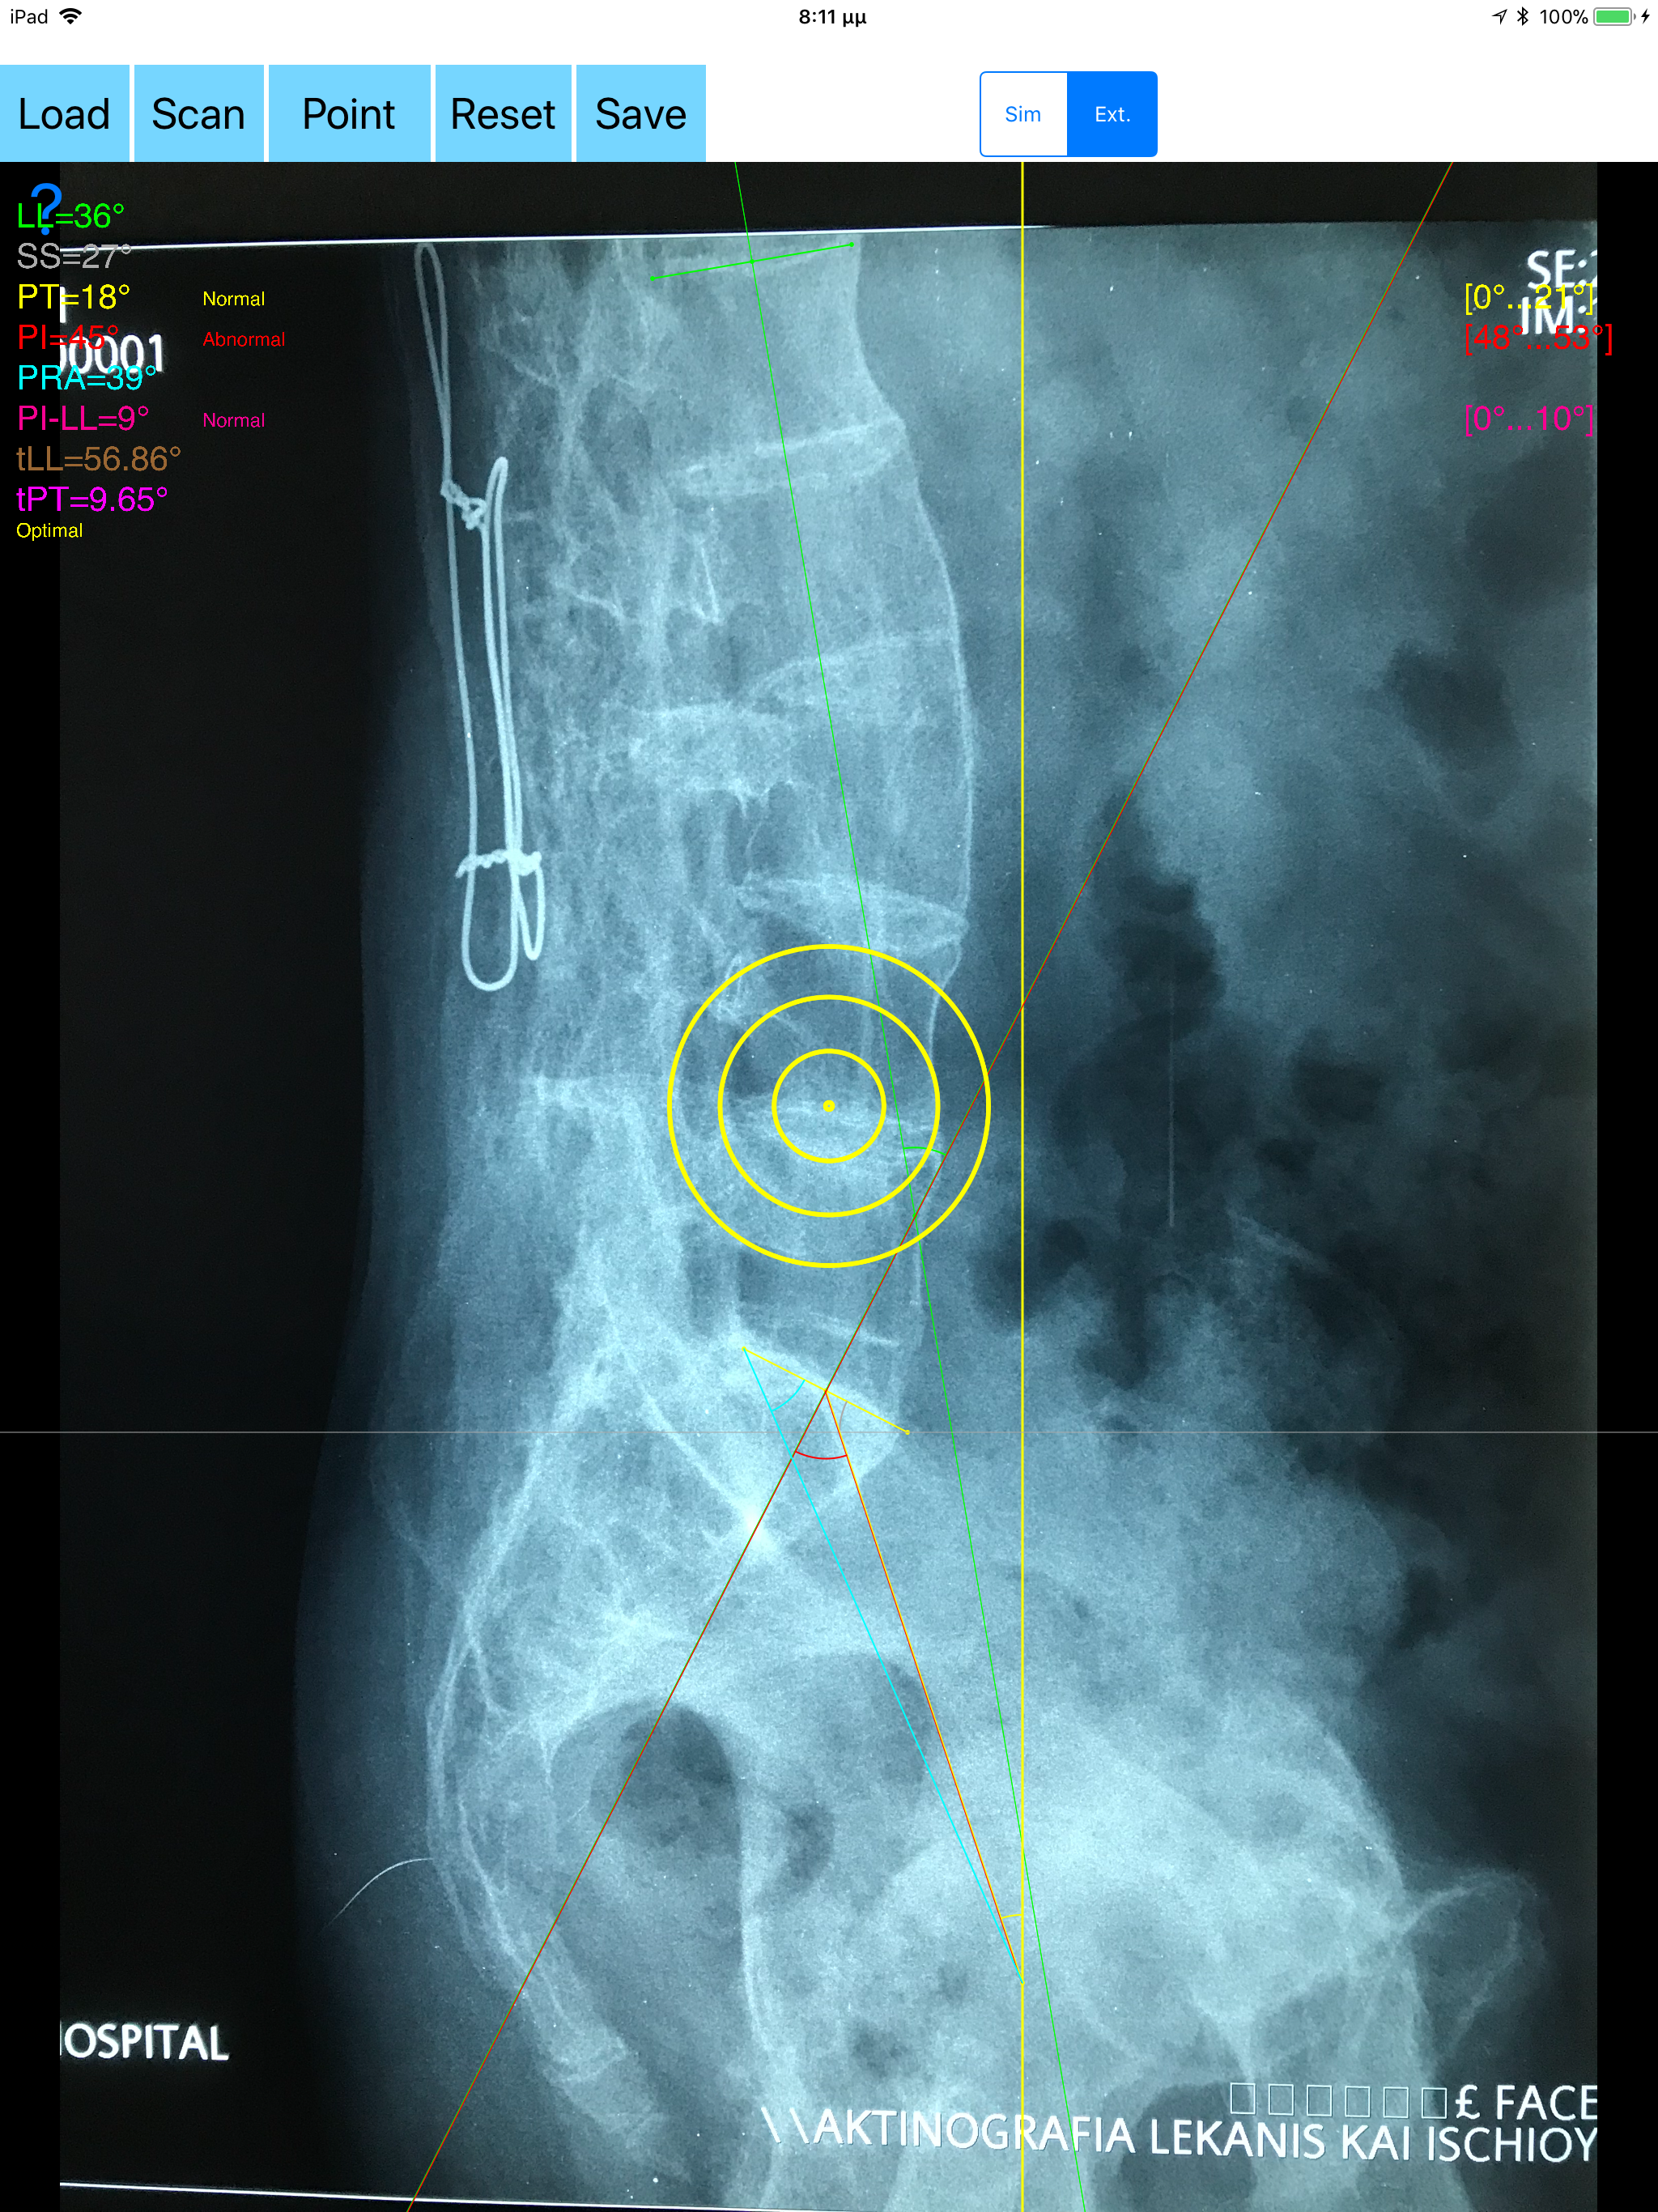

The assessment of the parameters involved in spinopelvic jucture are of paramount importance for spine and joint replacement surgeon. The dynamic interplay between flexibility and balance around the axis of gravity determine the type and the amount of influence in spine and hips. Radiographic parameters to evaluate objectively the spinopelvic sagittal balance are Pelvic incidence (PI), Sacral slope (SS), Pelvic Tilt (PT), Lumbar lordosis (LL). Drawings in patients X-rays and precise measurements are important in order to quantify the magnitude of spinal deformities, to monitor the success or failure of treatment and thus optimise the management of patients according to the severity of the imbalance or even to identify patient at risk of degenerative spondylolisthesis or disk herniation. The Spinopelvic Balance App is medical software aimed for orthopaedic surgeons, providing tools that allow doctors to: -Securely import medical images directly from the camera or stored photos. -By marking few points at the image of X-ray, the App calculates and offers a very convenient way to determine the most accurate possibly way at once, Pelvic incidence (PI), Sacral slope (SS), Pelvic Tilt (PT), Lumbar lordosis (LL), thoracic kyphosis, PI–LL Pelvic incidence Angle (PI) minus Lumbar lordosis Angle (LL) PI–LL, theoretical normal pelvic tilt (tPT),theoretical normal L1-S1 lumbar lordosis (tL1S1), Pelvic Radius Angle (PRA). According to measured parameters the app categorises the severity of the imbalance of spine, in different stages: optimal or non optimal. -Save the planned images, for later review or consultation.The measured values are compared by normal reference databases and also data are exported as txt file, ready to print or to input as cells to excel for research. -The app allows choosing between simple and extended method according to everyday preference and also by choosing points in vertebra body in a independent manner from order. -The app can be used to measure L5 Incidence (L5I) Angle or L4 respectively. -The app offers theoretical value estimation this is particularly useful because a sensible difference between theoretical value and measured value reveals a compensation phenomenon if the pelvis tilt (PT) is higher than its theoretical value, then it is due to pelvis retroversion, which is a compensation phenomenon. Knowing the theoretical value of Pelvis Tilt (PT) provided it is easy to understand that a sensible difference between theoretical value and measured value is a compensation phenomenon. All information received from the software output must be clinically reviewed regarding its plausibility before patient treatment! Spinopelvic Balance App indicated for assisting healthcare professionals. Clinical judgment and experience are required to properly use the software.The software is not for primary image interpretation. In a busy everyday practice, the examiner have to draw lines in X-rays or in clinical settings, this it is time consuming and cumbersome. Accessory instruments like protractors, hinged goniometers, well sharped pencils, rulers or even transparent papers must be available. The app offers a very convenient and accurate way to perform most common radiographic measurements for spine, at the spinopelvic juncture in a blink of an eye in front of your screen. The build in feature of the app, allows results to be categorized may help decide what could be considered normal or pathologic. The app is not a simple goniometer, is an enhanced product which helps to monitor objectively the course of the treatment and evaluate optimally the spine. This App is particular useful in clinical settings where you need a quick results without losing time.Please see tutorial videos at the developer’s web Reference 1.Nunes VR, et al.Spinopelvic balance evaluation of patients with degenerative spondylolisthesis L4L5 and L4L5 herniated disc who underwent surgery.Rev Bras Ortop. 2016 Sep 22;51(6):662-666.